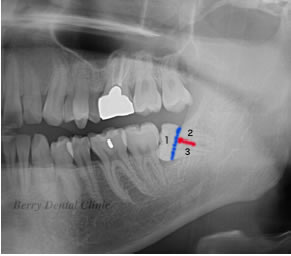

親知らずの抜歯の手順について

局部麻酔(伝達麻酔と浸潤麻酔)を施します。

親知らずを1、2、3、と番号順にカットしていきます。

順番に取り除いていきます。

この画像では1の部分を取り除きました。